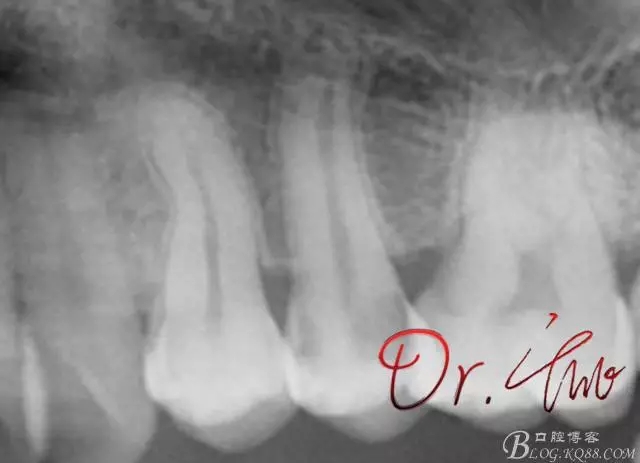

試主尖,近中頰側(cè)再次拍片查看臺階位置及確定長度

640.webp (8).jpg

試主尖,近中頰側(cè)試主尖,此時手用銼02錐度的已擴到30號,可以明顯感覺到臺階位置,挫預(yù)彎后找好正確位置可順利到達根尖,但是機用銼就是下不去,也是郁悶

最后根充,明顯可看到臺階位置,期待預(yù)后效果

640.webp (11).jpg